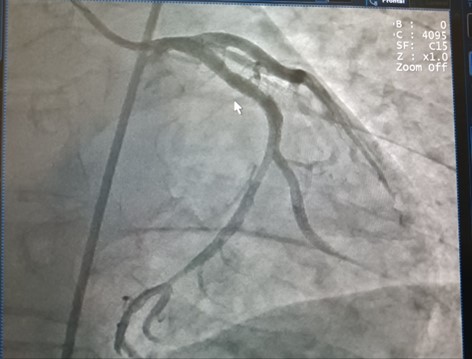

Sau đó, bệnh nhân được đưa vào phòng Can thiệp để tiến hành chụp động mạch vành và phát hiện có huyết khối gây tắc động mạch mũ, có chỉ định đặt stent. Tuy nhiên, trong quá trình can thiệp, bệnh nhân liên tiếp ngưng tim, ngưng thở thêm 4 lần nữa và rơi vào trạng thái hôn mê sâu. Để cứu sống bệnh nhân, Ê kíp bác sĩ vừa ép tim ngoài lồng ngực vừa sốc điện, vừa tiến hành can thiệp động mạch vành khẩn cấp cho bệnh nhân. Sau 10 phút nghẹt thở và căng thẳng, ê kíp các bác sĩ đã hồi sức cấp cứu và can thiệp thành công, lấy huyết khối, đặt stent tái thông động mạch vành cứu sống bệnh nhân.

Hình ảnh động mạch vành của bệnh nhân sau can thiệp